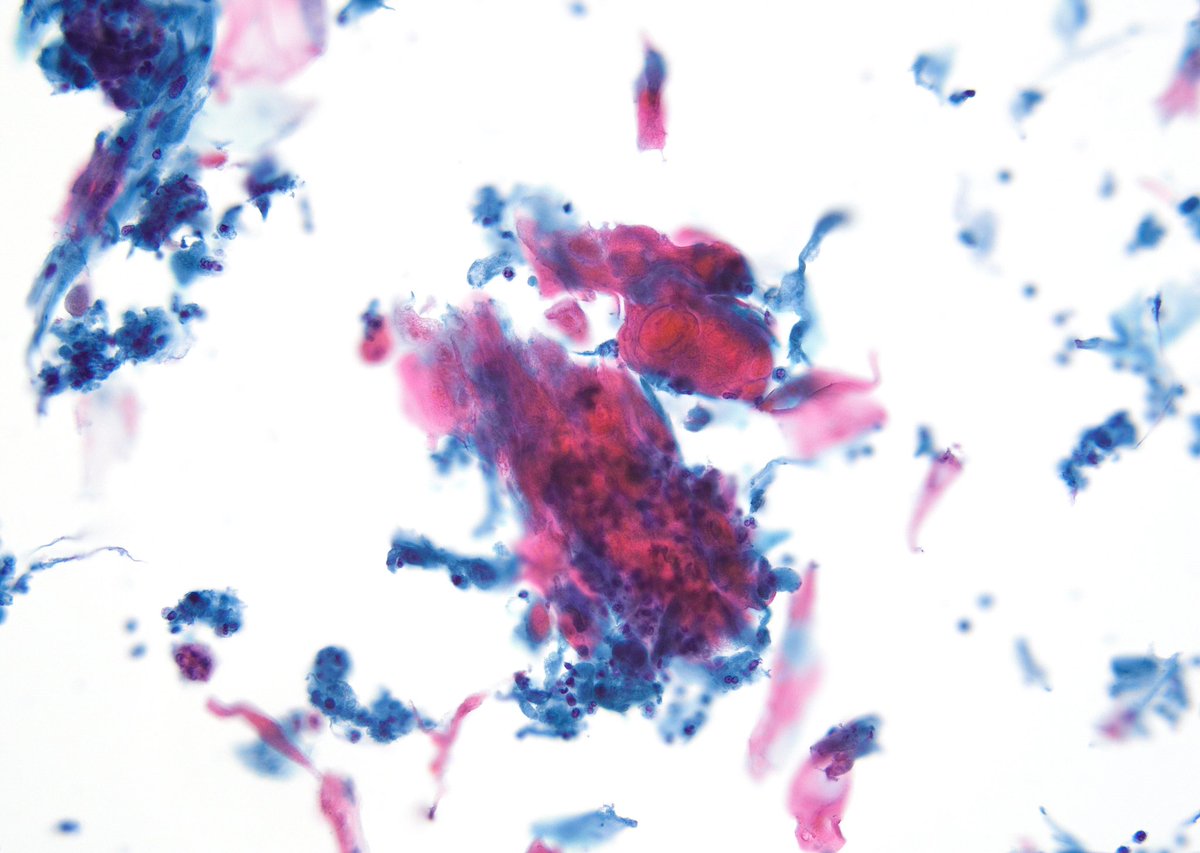

"BOW TIE". Papillary thyroid carcinoma. #FNA Thyroid. #Entpath #endopath #pathology #pathtwitter #PathTweetAward @MSWPathology @MyCytopathology @SamKhader